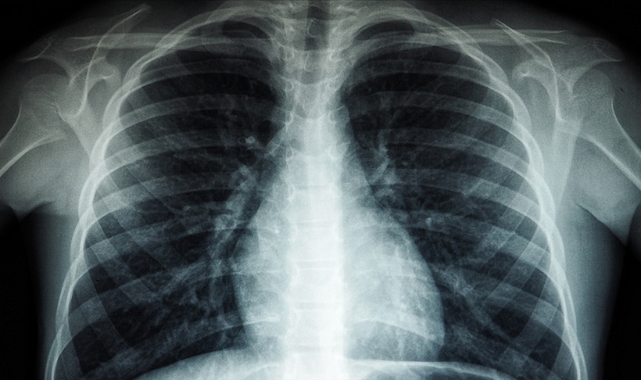

Düşük maliyetli bir ilacın Kovid-19 hastalarında akciğer zararını sınırladığı belirlendi

Bilim insanları, düşük maliyetli ve yaygın olarak kullanılan bir antiviral ilacın Kovid-19 hastalarında akciğer zararını sınırladığını tespit etti.

Australian National University ile King’s College London’dan araştırmacılar, oldukça yaygın olarak kullanılan, düşük maliyetli antiviral Heparin'in ağır enfeksiyondan muzdarip hastaların tedavi seçeneklerini artırdığını gösterdi.Heparin’den belli bir miktar soluyan hastaların nefes almalarının ve oksijen seviyelerinin yüzde 70 iyileştiğini belirleyen araştırmacılar, ilacın antiviral, iltihap önleyici ve kan sulandırıcı etkilerinin Kovid-19’un tedavisiyle bağlantılı olduğunu belirtti.Araştırmacılar, ağır Kovid-19 hastalarında akciğerlerde kan pıhtıları oluşması nedeniyle, Heparin’in kan sulandırıcı etkisinin bu tür pıhtıların oluşumunu engelleyebileceğini aktardı.Çalışmada yer alan kişilerin hastalık seviyelerinin farklı şiddette seyrettiğine dikkati çeken araştırmacılar, bunun antiviral özellikleriyle bağışıklık sistemini yatıştıran ilacın hastalığın genelinde güvenli ve etkili olduğunu gösterdiğine işaret etti.Araştırmanın baş yazarı Profesör Frank van Haren, Heparin’in özellikle düşük gelirli ülkelerde Kovid-19’un tedavisinde maliyeti az, güvenli, etkili ve ümit verici bir imkan olacağını vurguladı.Bilim insanları, 13 ülkede, Kovid-19 nedeniyle hastanede tedavi gören ve heparin verilen hastaları takip ederek araştırmalarını ilerletiyor.